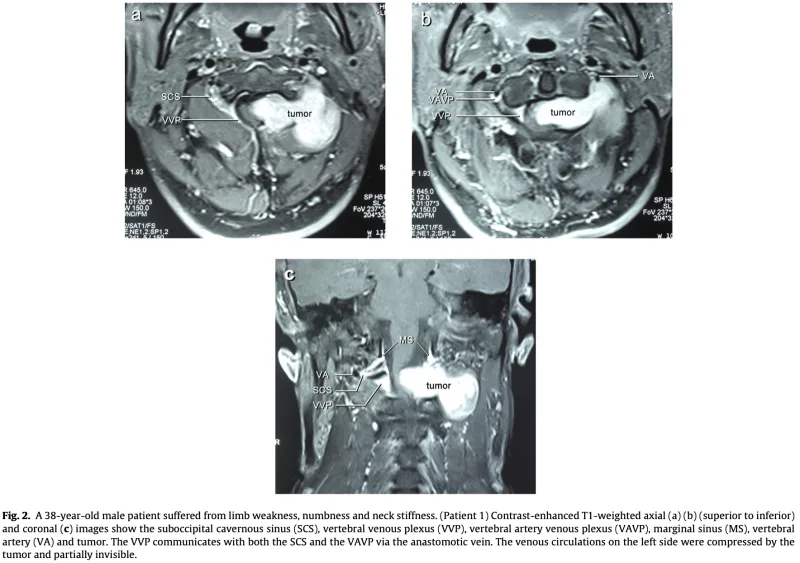

頚椎ダンベル腫瘍

形成外科から, 頚部腫瘍を指摘された中高年の患者さんが紹介され, 受診されました.

「MRIで, 頚髄とつながっているように見える」

との情報でした。

MRIでは, 第1/2頚椎椎間孔から頚部後方へ隆起する腫瘍性病変を認め, 第2頚神経根から発生した神経鞘腫 と診断しました.

脊柱管内から神経根に沿って椎間孔を通り, 外側(傍脊柱)へと砂時計状に広がる腫瘍は, その形状からダンベル腫瘍と呼ばれます.

多くは良性の神経鞘腫です.

脊髄や神経根が圧排されると, 感覚障害, しびれ, 筋力低下などの麻痺症状を呈しますが, この患者さんは幸い, 現時点では症状は認められませんでした.

大学病院の整形外科および脳神経外科での精査・治療を勧め, 予約を取りました.